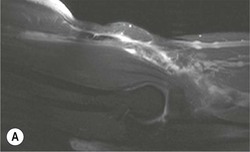

The distal biceps tendon inserts on the tuberosity of the proximal radius. It does not have a tendon sheath, but surrounding connective tissue is known as a paratenon. It is surrounded near the insertion by the bicipitoradial bursa. Distal biceps tears are often clinically unrecognised, but may be amenable to surgery if diagnosed early. In the early stages the tendon is thickened and there may be an effusion in the bicipitoradial bursa (Fig. 46-18). In complete rupture the tendon retracts proximally. MRI and US may be used to confirm the diagnosis and locate the tendon end (Figs. 46-19 and 46-20).